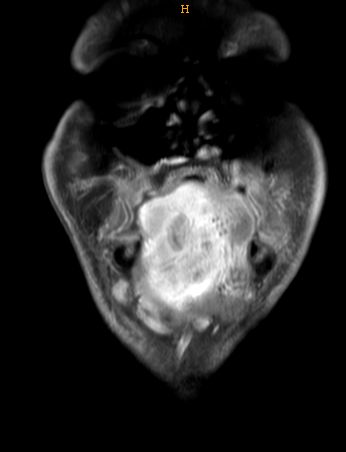

| MRT | Mundbodenkarzinom rechts T4 N2b Mo![]() ![]() ![]() |

||